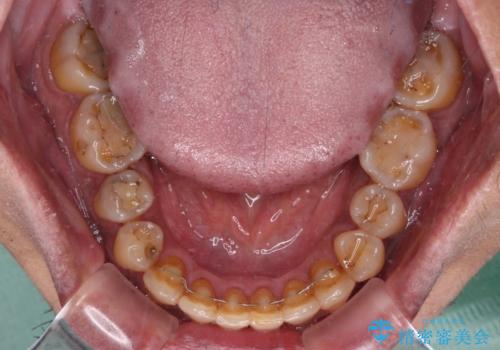

前歯のクロスバイトを改善 ワイヤー装置での非抜歯矯正

- 骨格的な咬み合わせのズレ、前歯のデコボコとクロスバイトを気にして来院された患者様です。

骨格のズレが顕著であると診断され、マウスピース矯正では奥歯の咬み合わせが整えにくいと判断し、ワイヤー装置による矯正治療を行うこととしました。

上下の叢生は速やかに改善できましたが、右側のクロスバイトの改善に1年以上の期間を要しました。